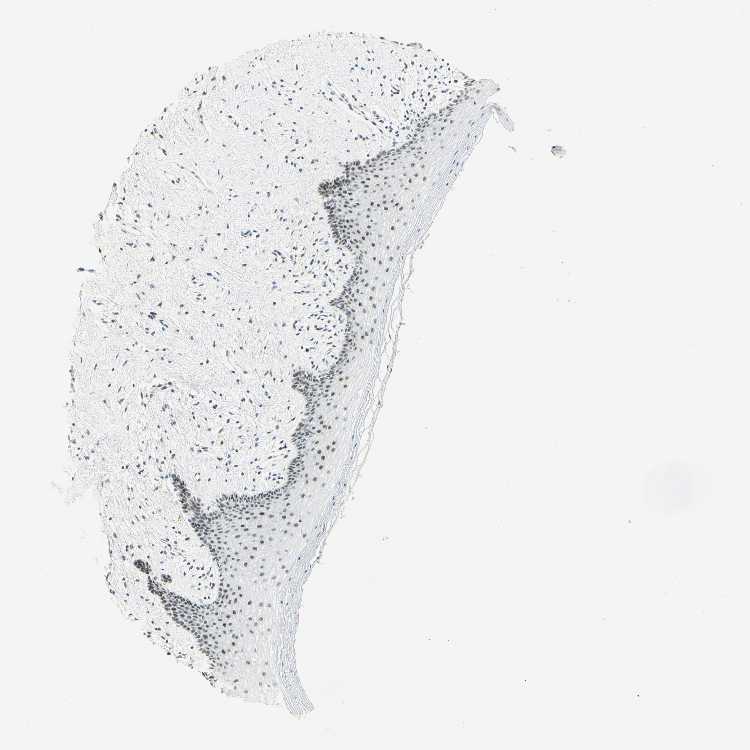

VAGINA - Antibody stainingi

Antibody staining in the annotated cell types in the current human tissue is reported as not detected, low, medium, or high, based on conventional immunohistochemistry profiling in selected tissues. This score is based on the combination of the staining intensity and fraction of stained cells.

Each image is clickable and will lead to virtual microscopy that enables deeper exploration of all samples and also displays staining intensity scores, fraction scores and subcellular localization as well as patient and tissue information for each sample.

Antibody CAB010235

Squamous epithelial cells Low